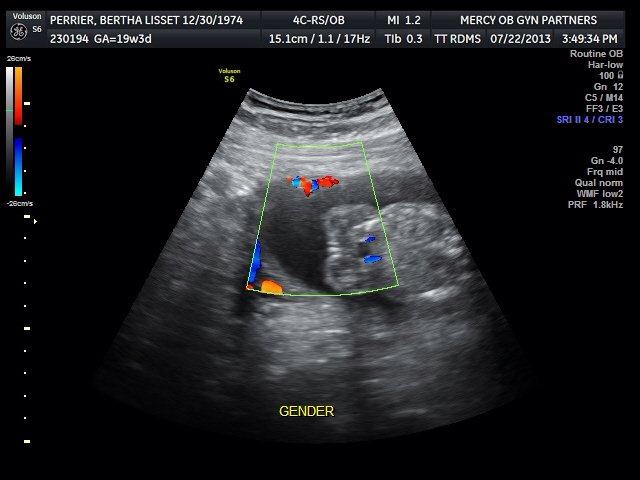

I had the same three lines for my girls.

That definitely looks like a girl to me.

oh defo girl